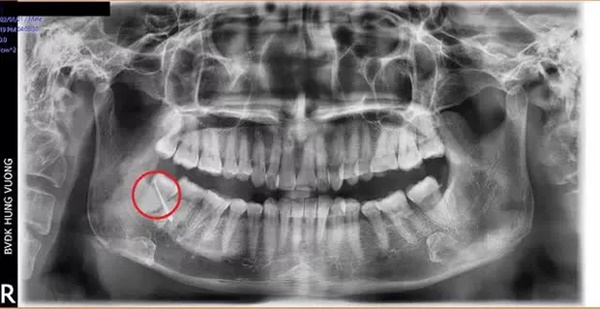

Đến Bệnh viện đa khoa Hùng Vương (Phú Thọ) thăm khám, bệnh nhân được chỉ định nhập viện điều trị ngay với chẩn đoán: Áp xe vùng má phải do răng số 48 mọc lệch.

Bệnh nhân đã được các bác sĩ Khoa Liên chuyên khoa thực hiện phẫu thuật cắt đường dò má và nhổ răng nguyên nhân.